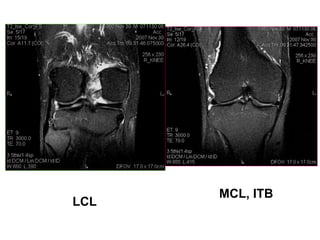

TOÅN THÖÔNG DAÂY CHAÈNG BEÂN

Ñoä 1: Taêng tín hieäu/ T2W ôû moâ phía trong daây chaèng

(giaõn daây chaèng möùc ñoä nheï).

Ñoä 2: Taêng tín hieäu/ T2W ôû moâ phía trong daây chaèng

vaø beân trong daây chaèng (giaõn daây chaèng möùc

ñoä trung bình) hay ñöùt moät phaàn daây chaèng.

Ñoä 3: Daây chaèng ñöùt hoaøn toaøn.

Toån thöông ñoä I MCL

Toån thöông ñoä II LCL

Toån thöông ñoä III LCL